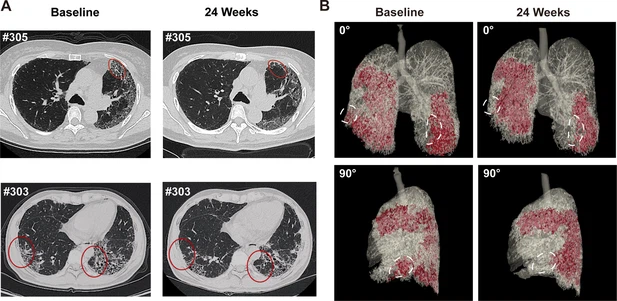

• 蜂窩狀病變消退:1M劑量組中兩名患者(#303、#305)的HRCT顯示下葉蜂窩狀病變減少(圖4A),三維重建證實下葉病變區域縮?。▓D4B)。

圖4:REGEND001治療前后的代表性肺部CT圖像。

(A) 患者#305和#303在基線和REGEND001治療后24周的代表性肺部CT圖像。紅色圓圈表示蜂窩狀病變消退。(B) 患者#305連續CT圖像的三維可視化。紅色區域表示細胞治療前后肺部受損區域(網狀和蜂窩狀)。白色圓圈表示下葉病變消退。

總結:REGEND001高劑量治療可顯著改善IPF患者運動能力及生活質量,并在部分患者中實現肺纖維化結構的可逆性修復(尤其下葉)。療效呈現劑量依賴性,且與細胞分布機制相關。盡管樣本量有限,但結果為再生療法逆轉肺纖維化提供了首個影像學證據,需擴大隊列驗證長期效果及機制。